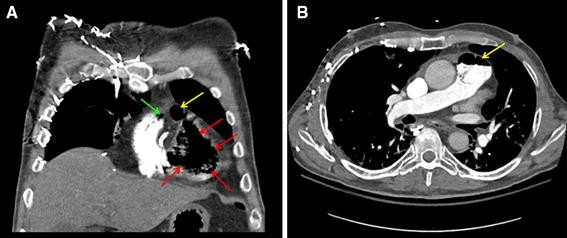

Massive Venous Air Embolism | SpringerLink

link.springer.com air embolism venous massive figure symptoms 1112

Pulmonary Infarction From Central Venous Air Embolism Mimicking Round

casereports.bmj.com venous thorax embolism pulmonary bmj pneumonia infarction casereports